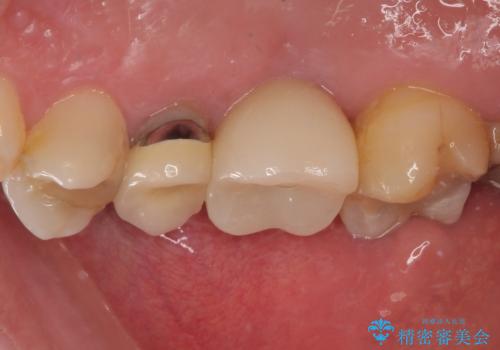

来院されるまではインプラント治療を躊躇されていましたが、抜歯即時埋入により、単回の外科処置で治療が終えられることのメリットを理解され、インプラントによる補綴治療を行いました。

スムーズに治療を終えることができました。